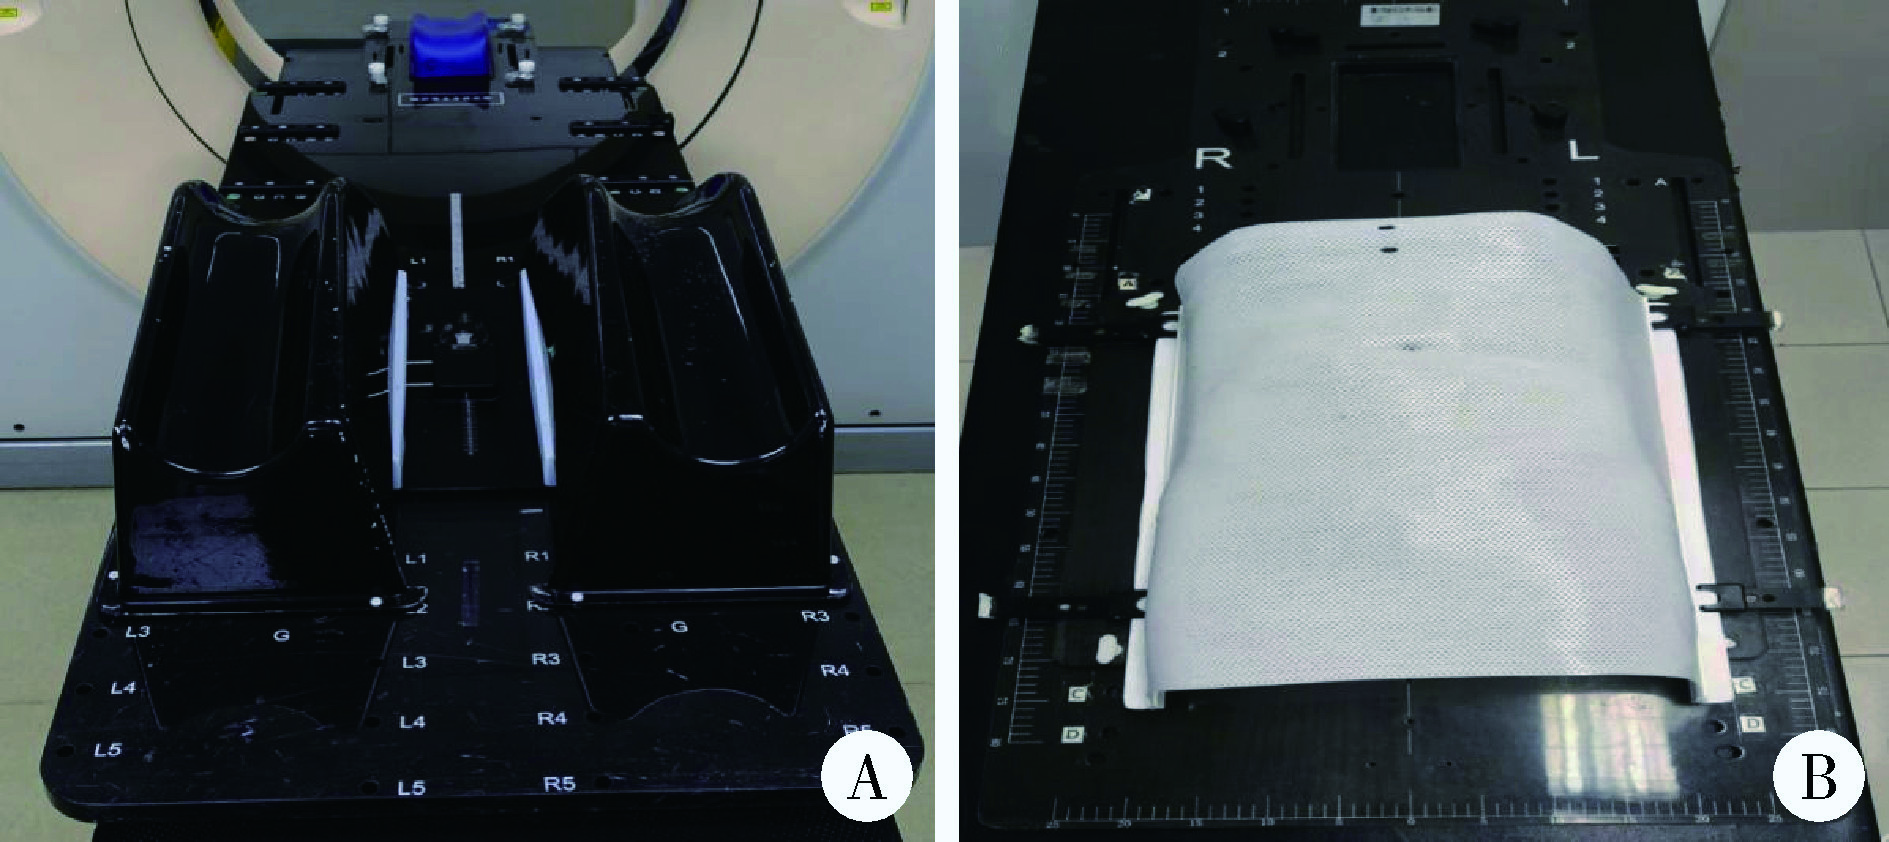

Comparison of setup errors between two immobilization methods in prostate cancer radiotherapy based on cone-beam computed tomography